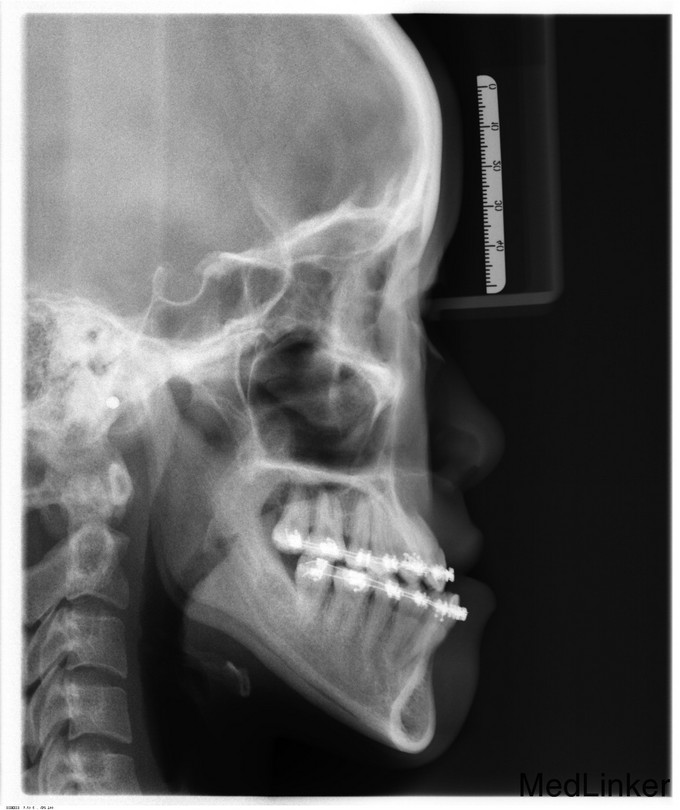

下颌前突十余年。青年女患者,慢性病程。患者于十余年前无明显诱因开始出现下颌前突,于去年11月份开始接受正畸治疗,2015-07-26入我院准备行正颌手术治疗,因感冒出院,今为进一步治疗来我院就诊,门诊以"下颌前突"收入院

面部发育良好,左右基本对称,上中下比例协调,面下三分之一过长前突左偏,颏顶点左偏,双侧颞下颌关节无弹响无疼痛,开口度3.7cm,开口型正常,上下牙弓关系不协调,中线不齐,前牙反牙合,后牙近中错牙合,左侧后牙反牙合,龋齿无,牙周病无。

诊断:下颌前突,全麻下行“双侧下颌升支矢状劈开后退术+双侧下颌骨去骨皮质术+双侧下颌骨骨内坚固内固定术+双侧邻近瓣转移修复术”,术后予消炎、消肿等对症治疗。

患者主要是单颌畸形,单纯运用矢状劈开就可以,不动上颌